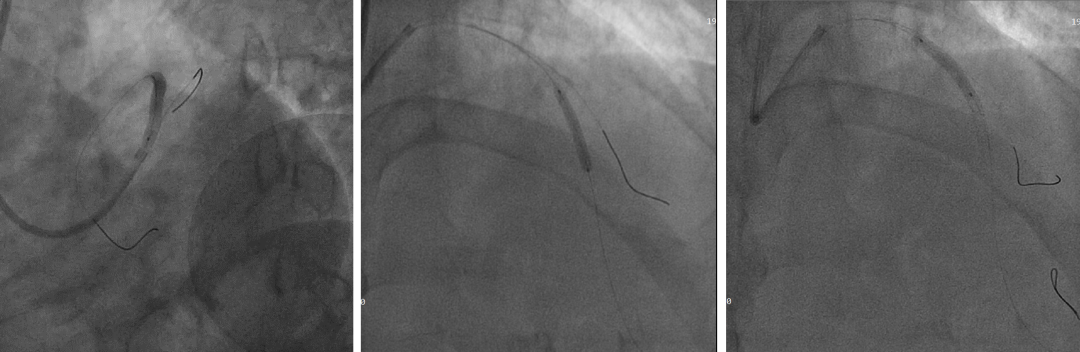

PCI过程

7F XB3.5,Cosair,Runthrough中间支保护,Pilot200正向进入D1,Pilot200 无法通过病变,交换Judo导丝

更换Judo3顺利到达LAD远端,Cosair跟进交换Runthrough

Ballon 2.0*15mm Dilatation & IVUS check

LAD-LM DES 2.75*20mm,2.75*18mm,3.0*30mm

Ballon 2.0*15mm Dilatation for D1 Ostial

NC Ballon & IVUS check

Final result:TIMI3